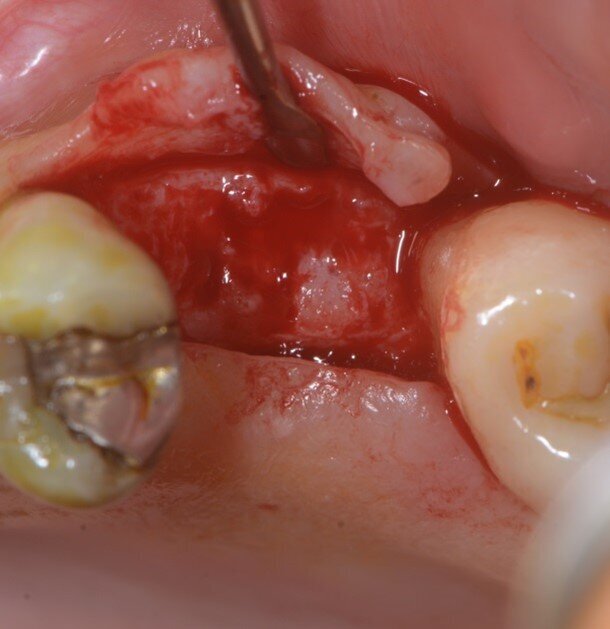

È stata eseguita una CBCT preoperatoria (Figg. 2a, 2b). La paziente, una donna di 52 anni in buona salute, ha iniziato la terapia antibiotica il giorno prima dell’estrazione con 2 gr. Amoxicillina e Acido Clavulanico. Dopo l’anestesia locale, è stata eseguita un’estrazione atraumatica cercando di non danneggiare le corticali ossee. L’alveolo è stato accuratamente pulito e risciacquato con acqua ossigenata e clorexidina 0,2% (Fig. 3). È stata praticata un’incisione intrasulculare sull’aspetto vestibolare dell’alveolo estrattivo, estendendosi al centro dei denti adiacenti. Un lembo a tutto spessore è stato sollevato ed il periostio staccato con micro-scollatori ha permesso di creare una busta per la lamina corticale (Fig. 4). La lamina corticale soft da 0,5 mm è stata prima idratata per cinque minuti in soluzione sterile e poi tagliata nella forma desiderata, tra 8 e 10 mm di altezza e con un’estensione che copre i margini mesiali e distali dell’alveolo estrattivo. La lamina corticale può essere facilmente inserita nel sito ed eventualmente ritagliata fino ad ottenerne un perfetto adattamento. I bordi devono essere rifiniti con angoli arrotondati per ridurre il rischio di perforazione e/o deiescenze sul versante vestibolare. La colla di fibrina umana (Tisseel, Baxter) è stata diluita al 10% mediante 0,9 ml di acqua bidistillata. Sulla lamina corticale sono state applicate due o tre gocce di colla, dopo di che la lamina è stata poi schiacciata con una gentile pressione digitale per adattarsi alla posizione predefinita (Fig. 5). Il lato palatale dell’alveolo è stato invece lasciato guarire per prima intenzione. Una spugna di collagene (Condress, Smith & Nephew) è stata inserita all’interno dell’alveolo per stabilizzare il coagulo ed è stata posizionata una sutura incrociata (4-0 punti di sutura in ptfe) per mantenere la spugna in posizione, le papille sono state invece suturate con due suture a fionda7 (Fig. 6). Quattro mesi dopo l’estrazione, prima di inserire l’impianto, è stata eseguita una CBCT post-operatoria per valutare la guarigione del sito operato.

Fig. 4 - Corticale vestibolare esposta.